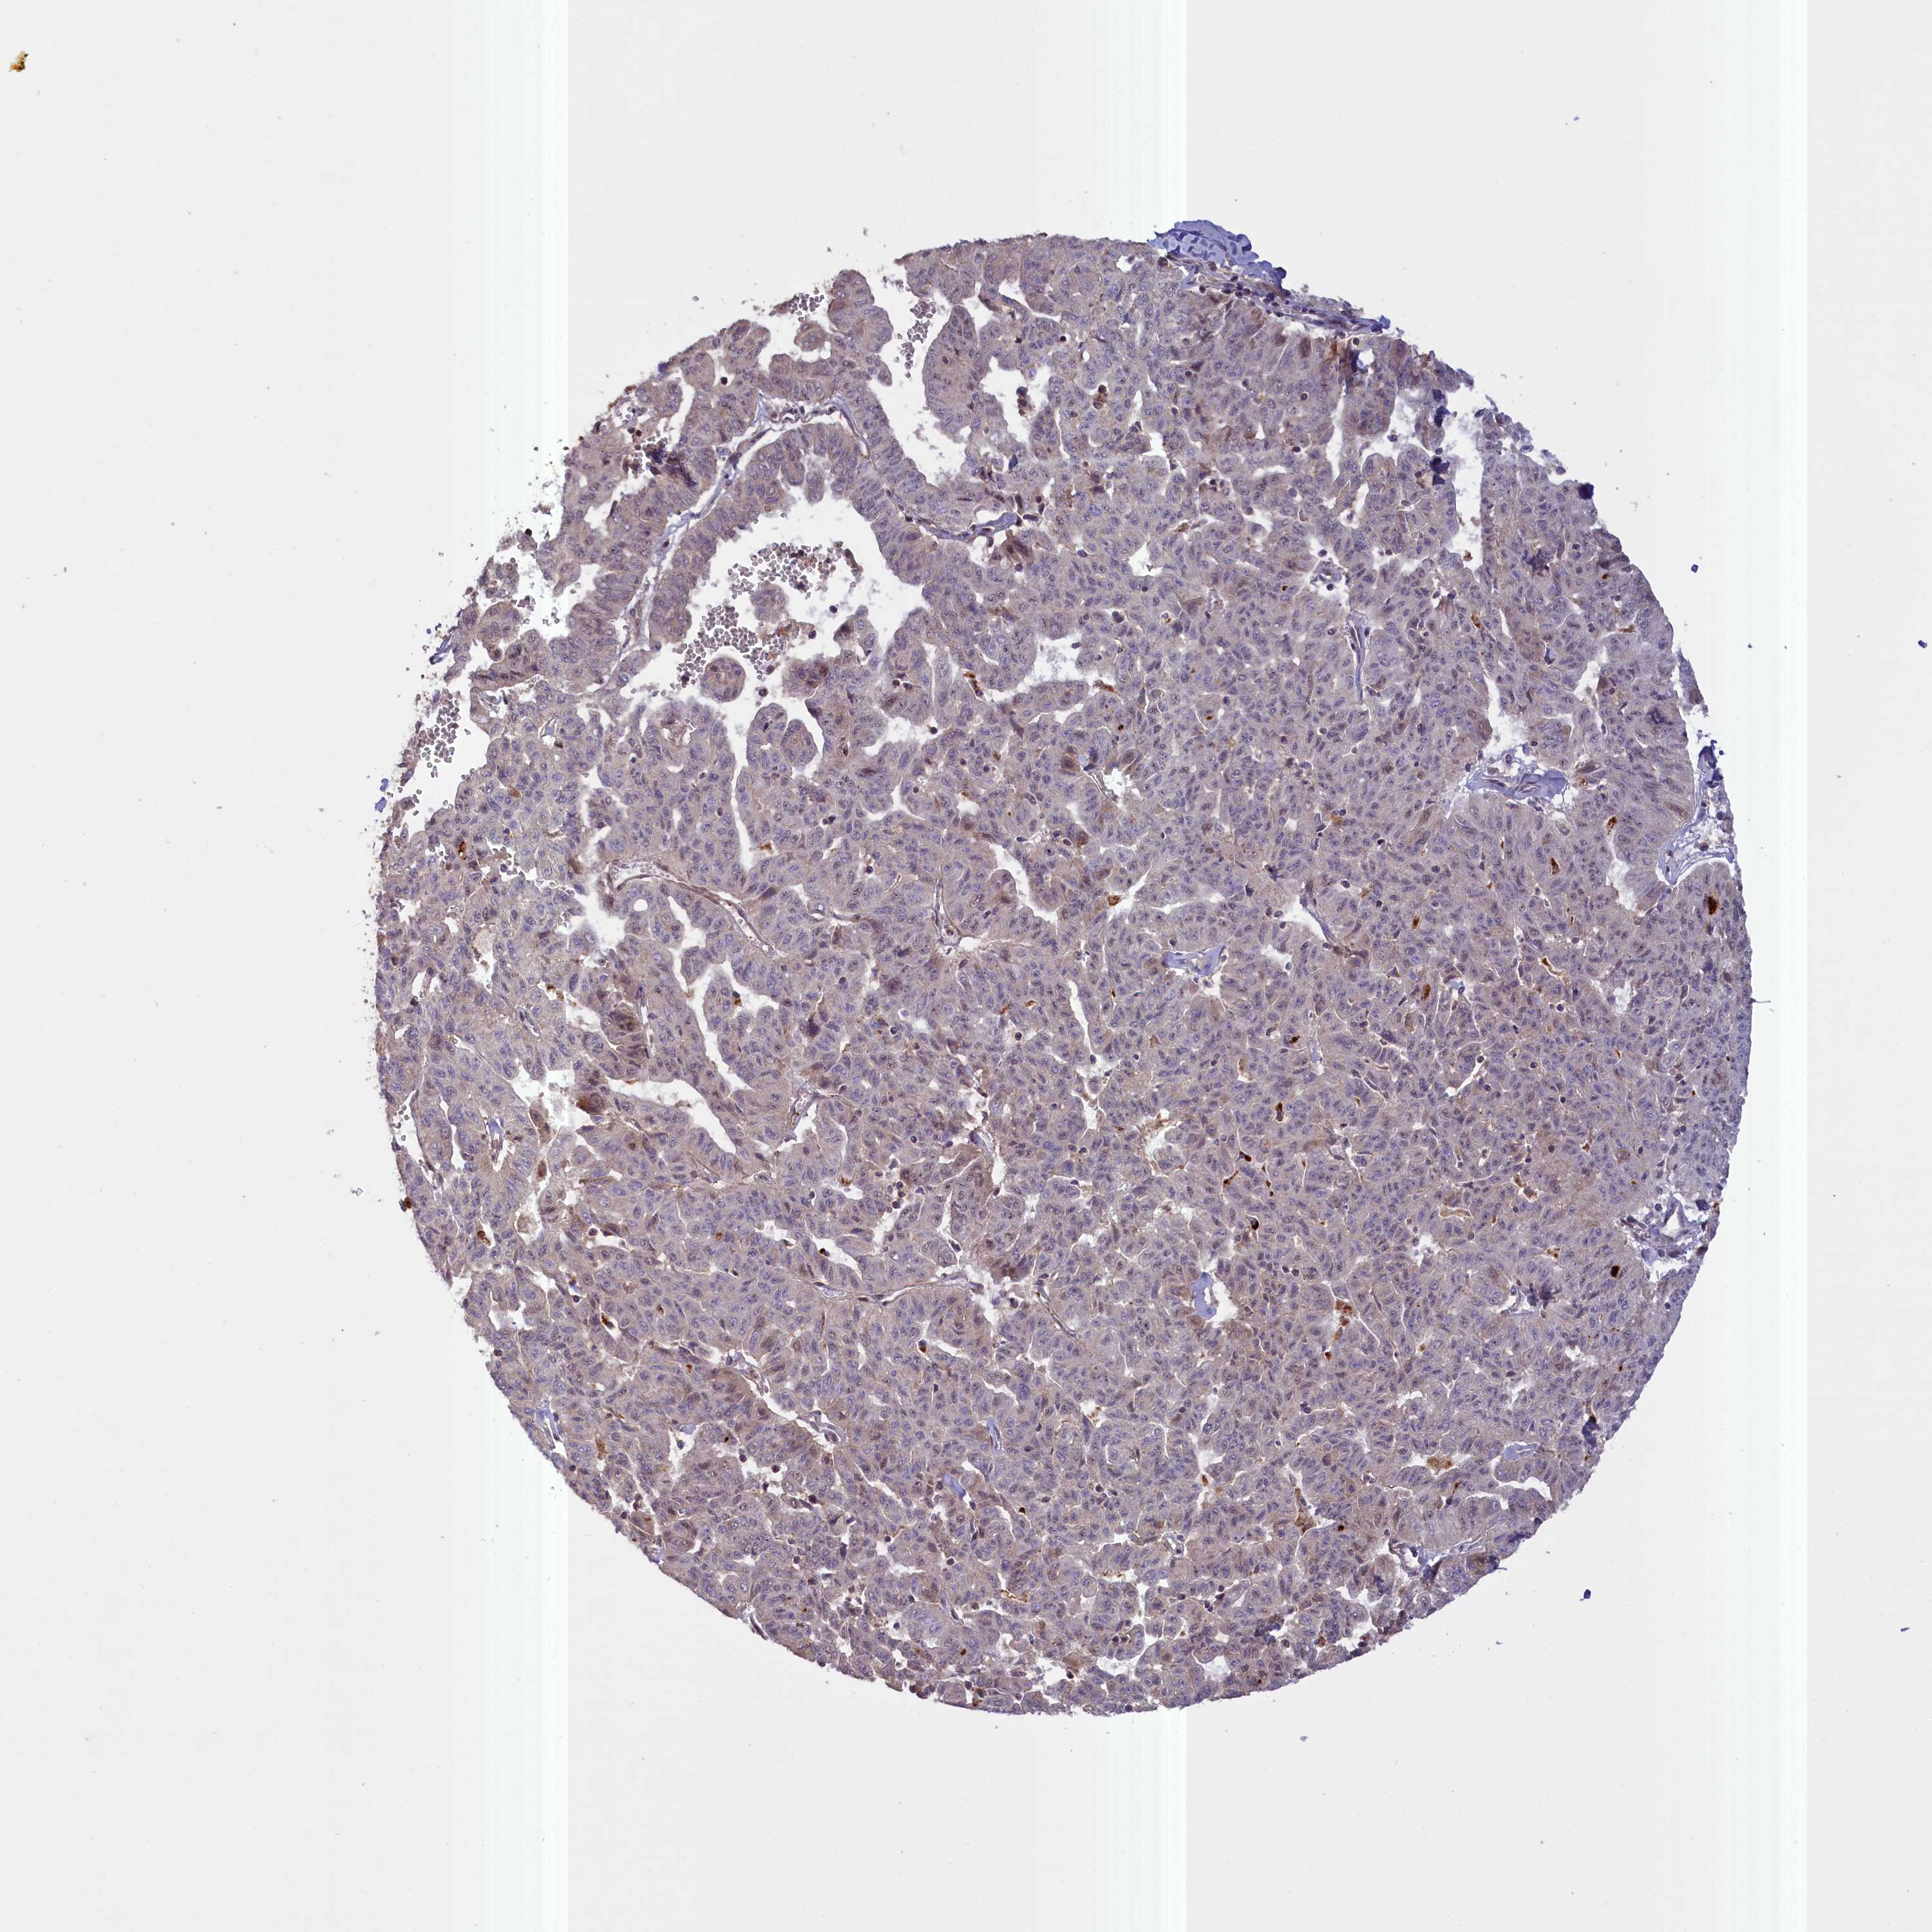

LIVER CANCER - Protein expressioni

A mouse-over function shows sample information and annotation data. Click on an image to view it in a full screen mode. Samples can be filtered based on level of antibody staining by selecting one or several of the following categories: high, medium, low and not detected. The assay and annotation is described here.

Note that samples used for immunohistochemistry by the Human Protein Atlas do not correspond to samples in the TCGA dataset.

Antibody stainingi

Antibody staining in the annotated cell types in the current human tissue is reported as not detected, low, medium, or high, based on conventional immunohistochemistry profiling in selected tissues. This score is based on the combination of the staining intensity and fraction of stained cells.

Each image is clickable and will lead to virtual microscopy that enables deeper exploration of all samples and also displays staining intensity scores, fraction scores and subcellular localization as well as patient and tissue information for each sample.

Antibody HPA041779

Antibody HPA042196

Staining

High

Medium

Low

Not detected

Intensity

Strong

Moderate

Weak

Negative

Quantity

>75%

75%-25%

<25%

None

Location

Nuclear

Cytoplasmic/membranous

Cytoplasmic/membranous,nuclear

Cholangiocarcinoma

Carcinoma, Hepatocellular, NOS